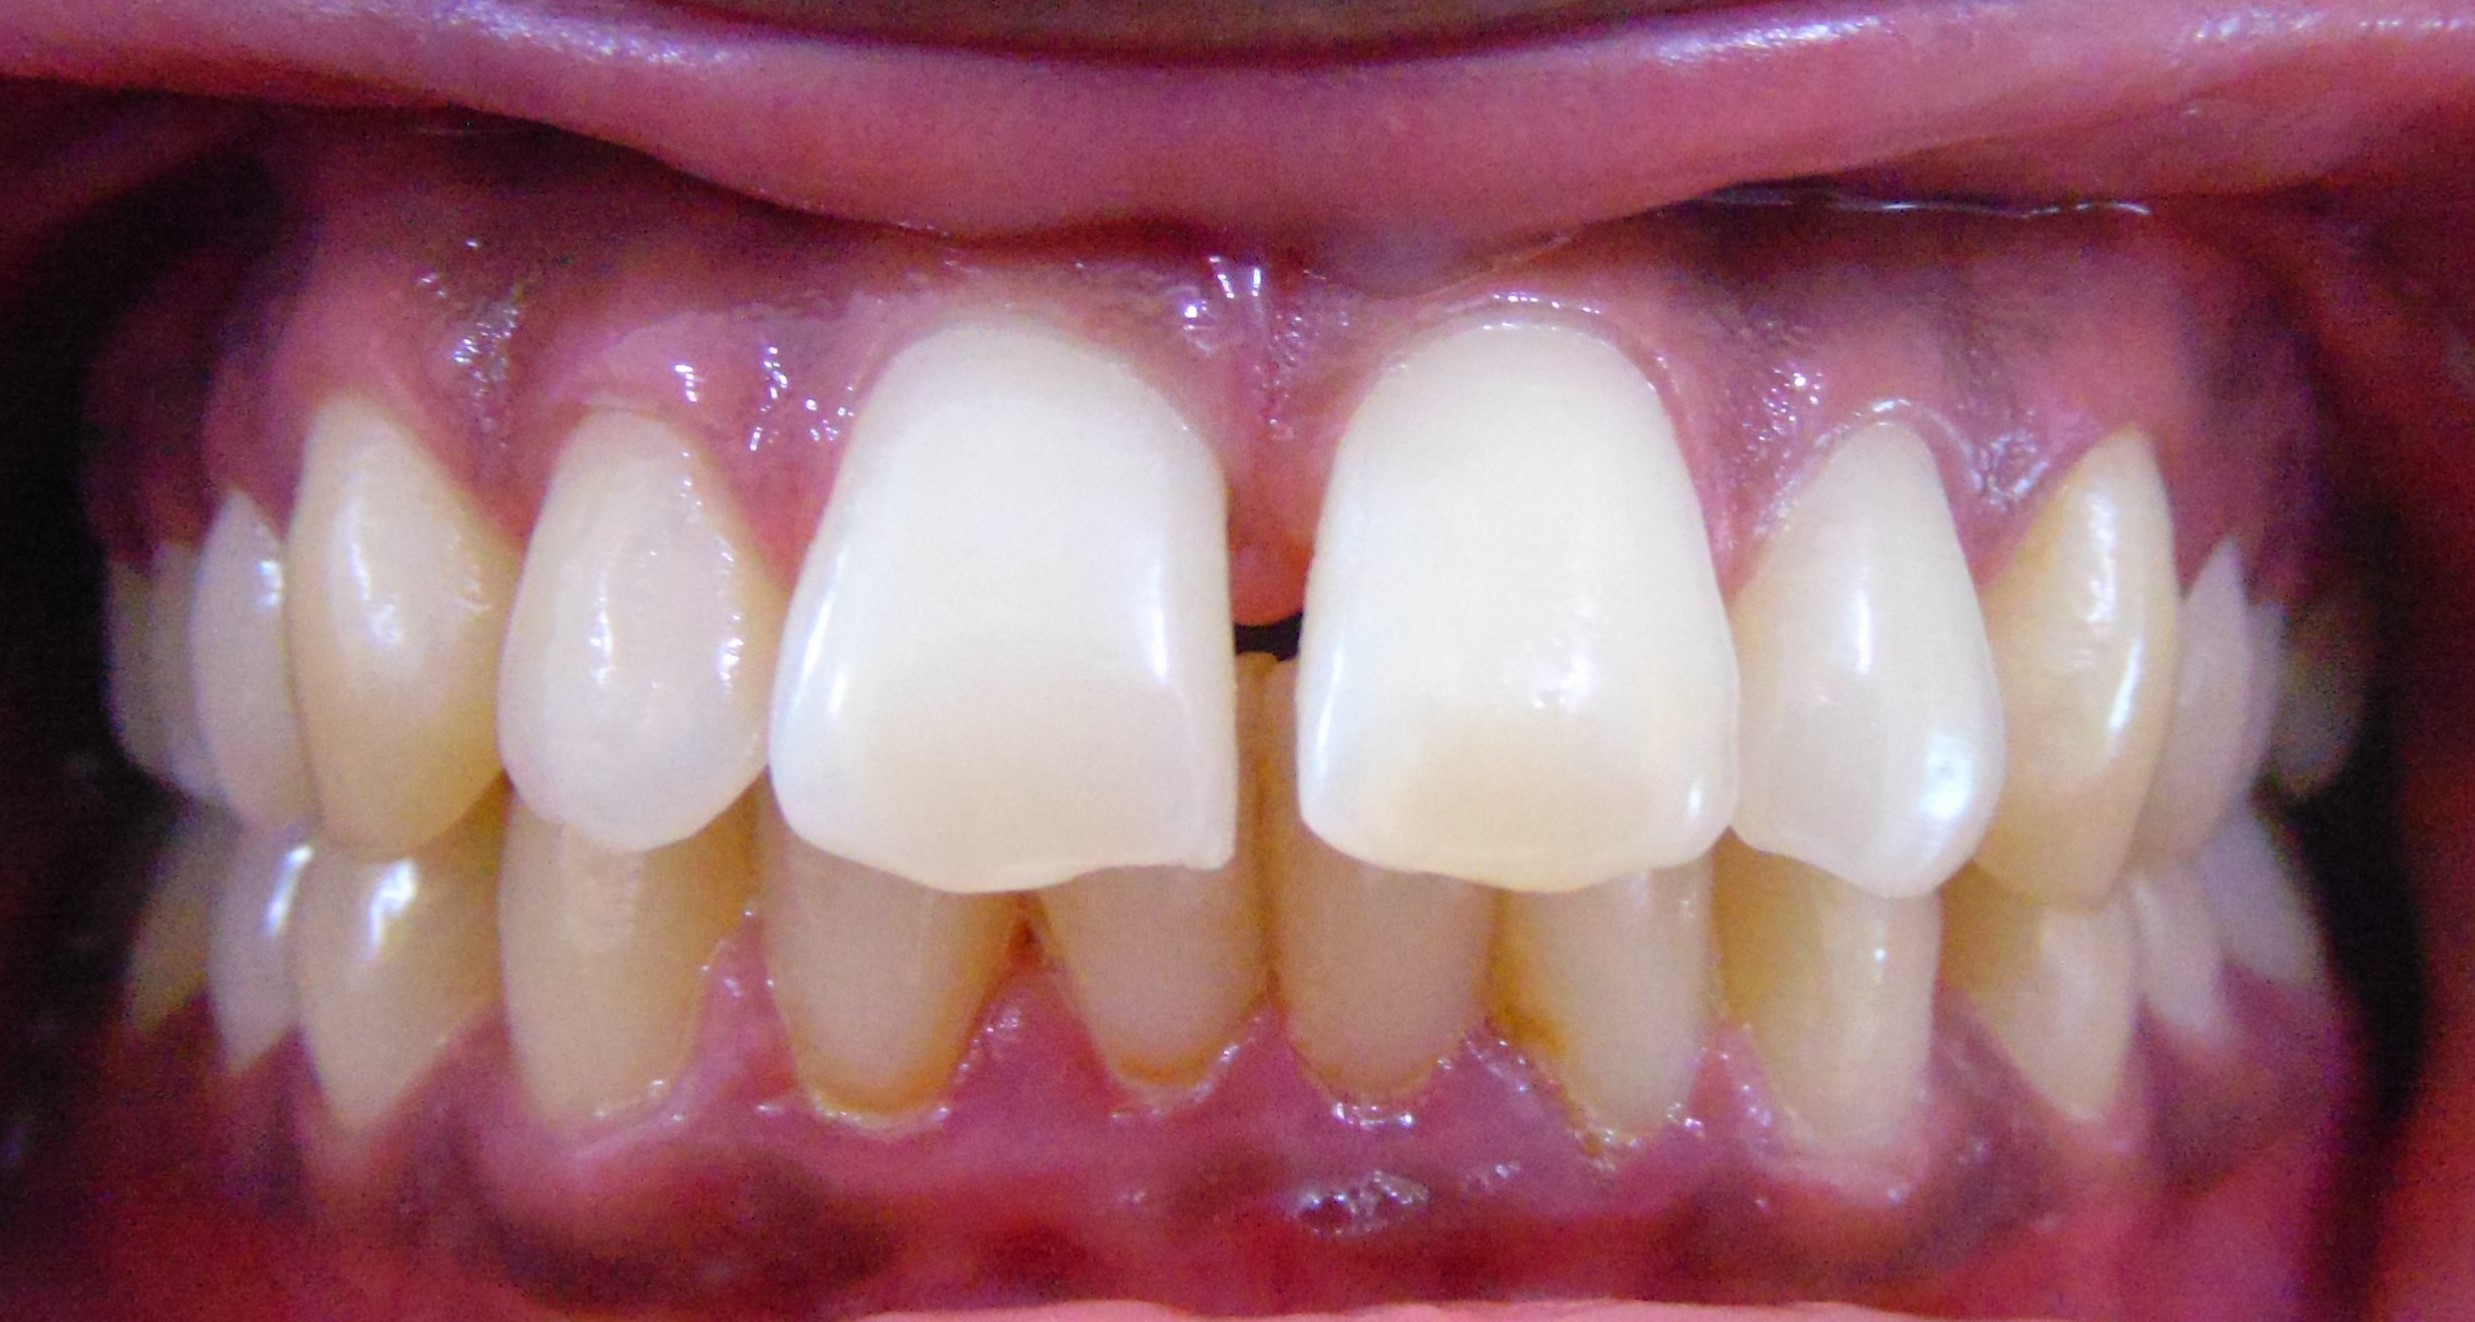

Akshay Jadhav, 30Y, Duration - 10Months

Before

After